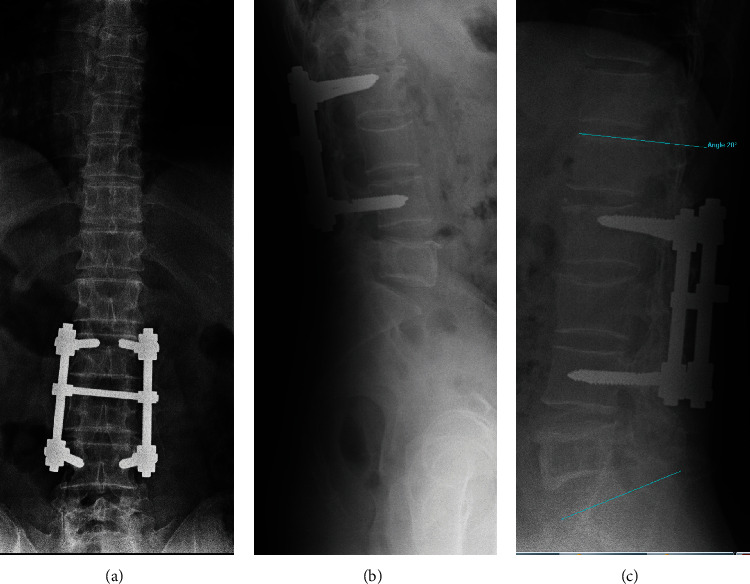

导言:描述一例罕见的成年腰椎椎体单发骨囊肿病例。单发性骨囊肿的定义是含液体的囊性病变。很少有病例描述椎体位置,而不倾向于后弓或椎体。大多数病例采用切除、刮除和/或植骨的方法进行治疗。迄今为止,还没有在椎体位置注射聚甲基丙烯酸甲酯(PMMA)的病例。病例介绍。一名 50 岁的男性患者因腰部疼痛就诊,无外伤史,无神经功能缺损。放射学检查显示,患者在二十年前曾因 L3 骨折而进行过腰椎关节置换术,并植入了 L2-L4 器械。计算机断层扫描(CT)显示,溶蚀性病变几乎占据了 L5 的整个椎体,椎间隙不完整,边缘硬化,皮质无破裂。为了避免在进行磁共振(MR)检查时出现伪影,患者移除了之前的钢制器械,并在同一次手术中经穿刺对 L5 椎体进行了活检。磁共振检查结果和活检结果均与单纯骨囊肿相符。最后,通过使用 PMMA 填充病变部位进行了新的干预。5年的随访结果令人满意,没有腰痛,放射学检查结果也是如此,患者恢复了以往的活动能力:结论:脊柱部位的单纯骨囊肿极为罕见。其诊断需要排除其他病变,并通过影像学检查和活组织检查来确定。治疗方法有切除术、刮宫术、植骨填充术或本例中的PMMA填充术。

Introduction: To describe a rare case of solitary bone cyst in the vertebral body of the lumbar vertebra in an adult patient. The solitary bone cyst is defined as a cystic lesion with liquid content. Few cases have been described in the vertebral location without preference for the posterior arch or vertebral body. Most have been treated with resection, curettage, and/or grafting. No case described to date has been treated with polymethylmetacrylate (PMMA) injection in the vertebral location. Case Presentation. A 50-year-old male patient was consulted for lumbar pain with no traumatic history and no neurologic deficit. The radiological study showed lumbar arthrodesis with L2-L4 instrumentation due to an L3 fracture twenty years earlier. Computed tomography (CT) scan showed a lytic lesion occupying practically the entire vertebral body of L5, with incomplete septum and sclerotic edge, without cortical rupture. The previous steel instrumentation was removed, to avoid the presence of artifacts when performing the magnetic resonance (MR), and a biopsy of L5 vertebra was performed via transpedicular in the same act. The MR study findings and biopsy were compatible with the simple bone cyst. Finally, a new intervention was performed by filling the lesion with PMMA. Follow-up at 5 years was satisfactory without lumbar pain as well as the radiological study and with a return to previous activity.

Conclusions: The spinal location of the simple bone cyst is extremely infrequent. Its diagnosis excludes other lesions and is made by imaging studies and biopsy. Treatment can be performed by excision, curettage, or filling with graft or as in this case, with PMMA.